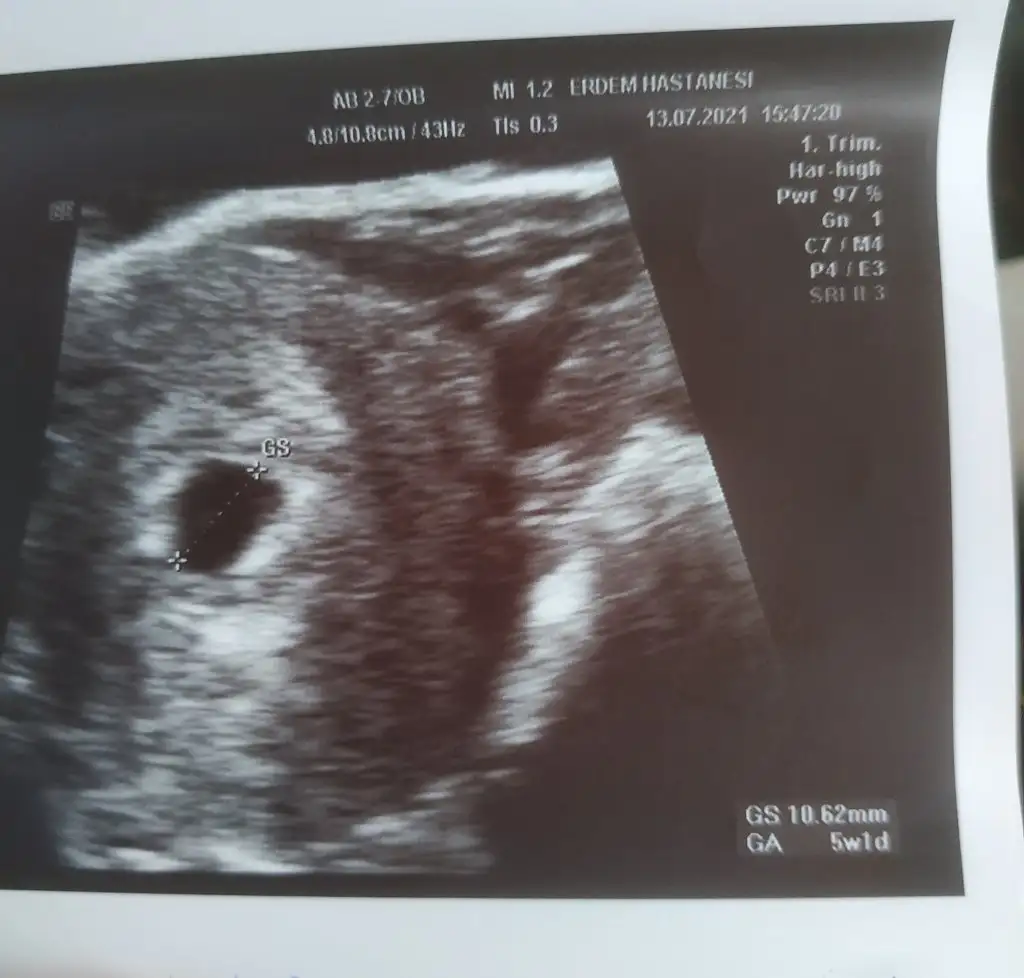

Kizlar çıktım doktordan 5+5 olması lazimken 5+1 çıktı . Keseyi ve yolk gördük bebisi vajinal da baksak göremeyiz dedi haftaya pztsi gidicem tekrar .kese gayet iyi 10 mm dedi

Oy maşallah, sağlıkla ilerlesin inşallah:) ben de yarın gidicem nasipse görmeye. Erdem hstde kime gittiniz memnun kaldınız mı? ben ilk sefer için ümran tıpa gidiyorum